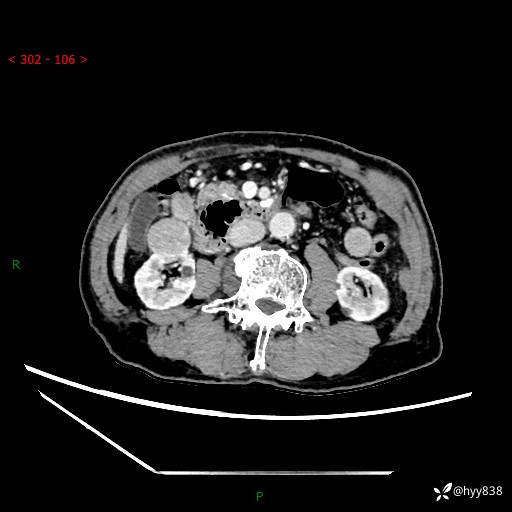

辅助检查:CT

肾脏CT平扫

增强(皮质期+髓质期+排泄期)

三期CT值:132hu 107hu 81hu